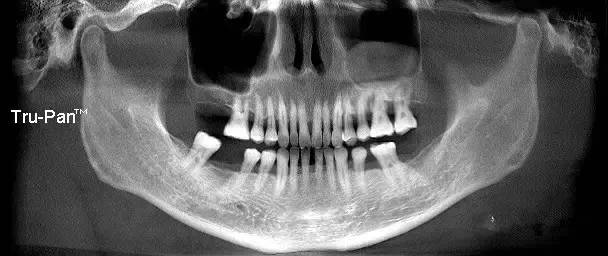

第三圖:上頜竇氣化導(dǎo)致上頜竇過大,上頜竇底骨質(zhì)向紙張一樣薄。只適合做外提升。